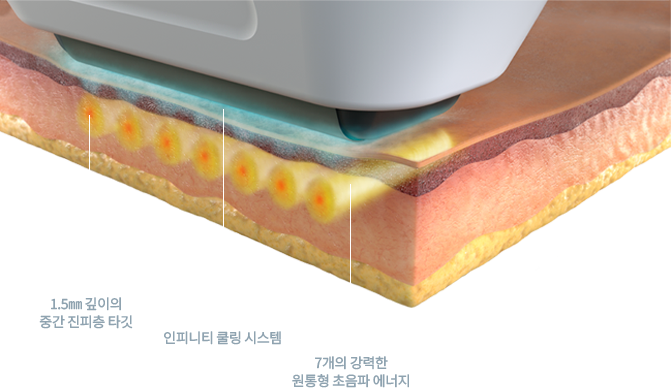

소프웨이브는 주름의 깊이 1.5mm에 최적화된 11.5MHz의 에너지를 7개의 트랜듀서로 강하고, 쿨링 시스템을 통해 피부 손상 없이 안전하게 탄력 개선을 위한 의료기기 시술입니다.

차별화된 1.5mm의 기적

소프웨이브 시술은 피부 진피층의 중간 깊이이자 주름이 생기는 근원인 1.5mm 깊이를 정확히 타겟하기 때문에 지방이나 근육 등 다른 조직 손상 염려를 최소화했으며 얇은 피부는 물론 눈가, 입가 등 기존 레이저 시술로는 적용이 불가능했던 부위까지 적용 가능합니다.

소프웨이브의 원리

Step 1.

피부 표피 손상을 완화시키면서

변화는 주름과 피부 처짐을 야기합니다.

-

Step 2.

피부 표면과 평행한 3D 원통형 열기둥을 생성합니다. 최적의 피부 자극을 위해 6~70도의 열 온도를 5초간 진피층에 노출시킵니다.

-

Step 3.

시술 후 조직 검사 결과 진피 중간층의 콜라겐이 증가, 진피 탄력섬유(elastic fiber)가 탄탄하게 재정렬된 것을 확인됩니다.